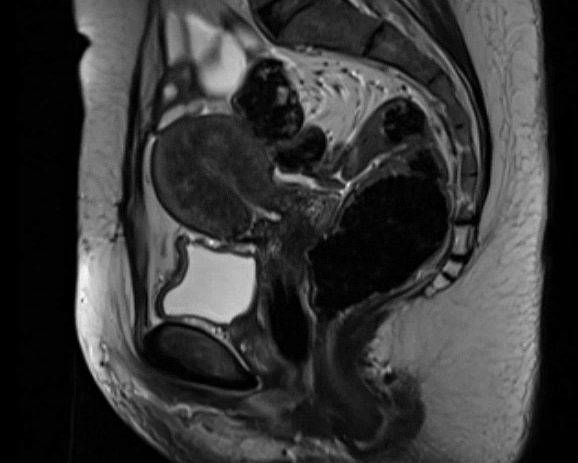

Hannah’s diagnostic interests are broad and include women’s imaging including breast radiology and placental and foetal MRI. Hannah performs a broad range of interventional radiology procedures including pulmonary embolus large bore thrombectomy, treatment of varicose veins, venous stenting, cyroablation, uterine fibroid embolisation and pain procedures.

Adenomyosis

Pelvic Congestion Syndrome